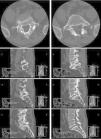

Since 1968, many surgical techniques used in repairing the pars defect of the vertebra have been reported. Technological advances are giving rise to new ways of obtaining the best outcome using less invasive methods, which are more accurate, simple and effective. To treat cases of spondylolysis such as pseudarthrosis, we used neuro-navigation and microscopy through a 2.5-cm skin incision to approach the pars defect, freshen the fracture and place a type of screw that, until now, has never been used for this purpose. This is a novel technique, which guarantees prolonged compression and sufficient stability to facilitate the prompt healing of the vertebra. We present 2 cases of L5 spondylolysis treated with our technique, a modification of Buck's technique. A detailed description of the screw selection, surgical technical details, follow-up and outcome are discussed.